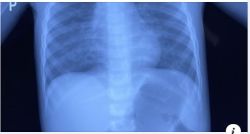

Không những thế, dùng gối cho trẻ sơ sinh còn ảnh hưởng đến sức khỏe của trẻ. Nếu cho trẻ sơ sinh nằm gối, sẽ khiến phần đầu của trẻ nhô cao hơn phần cơ thể, phần cổ bị động ép thành một đường cong, kết quả phần đầu nhô cao, phần cằm kề sát gần ngực, hậu quả là hạn chế khả năng hô hấp của trẻ, ảnh hưởng đến quá trình sinh trưởng của xương và cột sống.